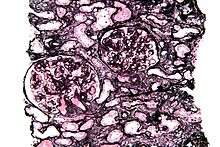

Micrograph of a kidney biopsy stained with a Jones stain.

Jones' stain, also Jones stain, is a methenamine silver-Periodic acid-Schiff stain used in pathology.[1] It is also referred to as methenamine PAS which is commonly abbreviated MPAS.

It stains for basement membrane and is widely used in the investigation of medical kidney diseases.

The Jones stain demonstrates the spiked GBM, caused by subepithelial deposits, seen in membranous nephropathy.